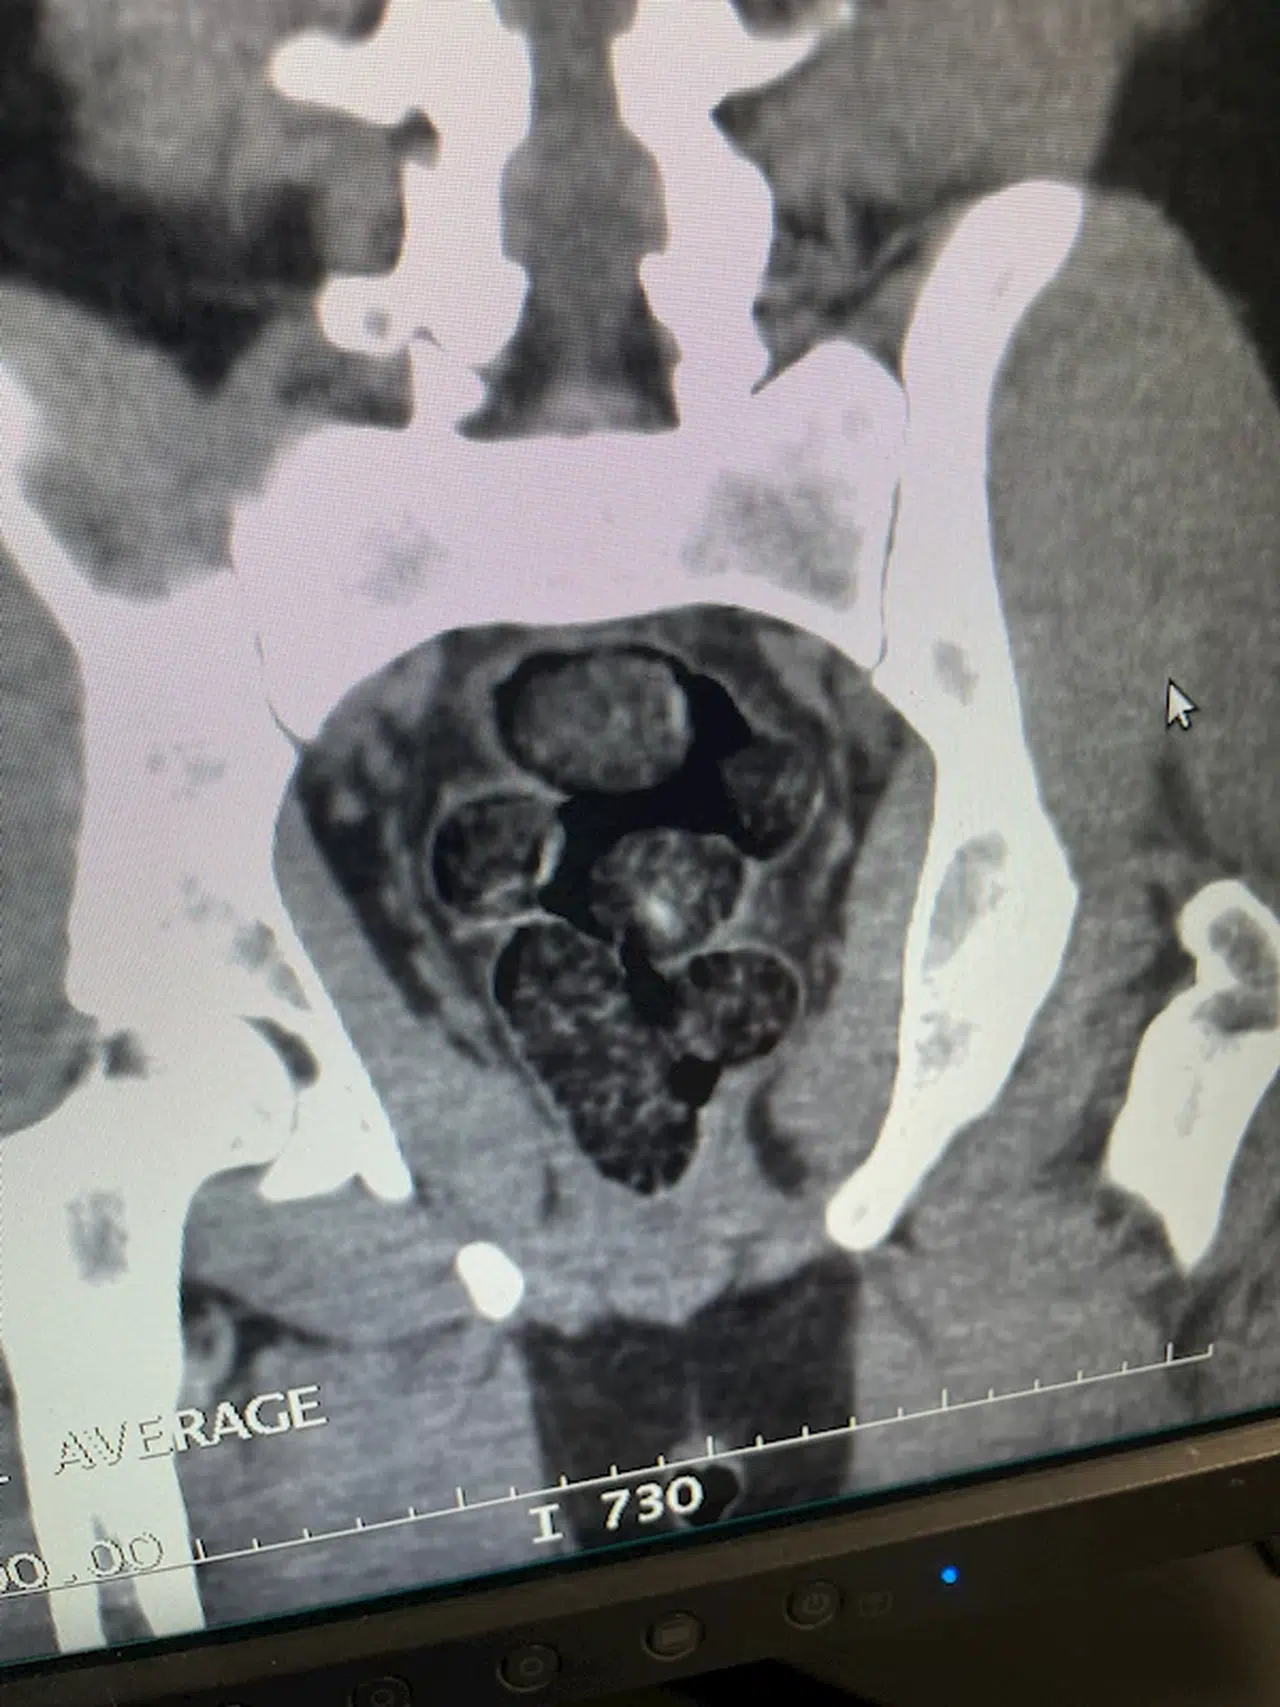

Mehmet Emin COŞKUNDERE/ÇARŞAMBA (Samsun), (DHA)- İRAN'dan Samsun'a gelen İran uyruklu Matin M.'nin midesinde poşete sarılmış, 10 adet olmak üzere toplamda 191,18 gram metamfetamin ele geçirildi.

İl Emniyet Müdürlüğü Narkotik Suçlarla Mücadele Şube Müdürlüğü ekipleri, İran'dan Ankara Esenboğa Havalimanı'na gelip, Samsun Çarşamba Havalimanı'na aktarma yapan İran uyruklu Matin M.'nin uyuşturucu taşıdığını belirledi. Takibe alınan şüpheli, Samsun'a iniş yaptığı sırada polis ekipleri tarafından yakalandı. Hastaneye götürülüp, tomografisi çekilen şüphelinin midesinden poşete sarılmış, 10 adet olmak üzere toplamda 191,18 gram metamfetamin ele geçirildi. Gözaltına alınan şüpheli, emniyete götürüldü. (DHA)